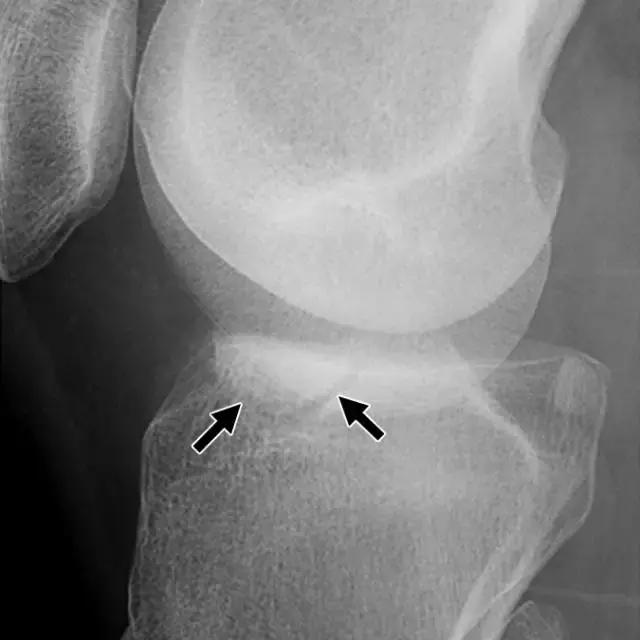

反向Segond骨折,是内侧胫骨平台的撕脱骨折,它是后交叉韧带严重受损的标志。这种骨折中的放射学检查结果与经典Segond骨折相似,只是反向骨折涉及胫骨近端的内侧(图6A)。据认为是由于内侧副韧带的深部荚膜组分的撕脱引起的(图6B),并且经常与内侧副韧带的严重损伤和相邻内侧半月板的周边损伤有关。

图6A -18岁的女性患有反Segond骨折。膝盖倾斜放射照片显示沿内侧胫骨平台的小撕裂性骨折(箭头)。

图6B,冠状脂肪抑制T2加权MR图像显示内侧胫骨平台内有明显的骨髓水肿,与内侧副韧带深部囊膜组分相关的反向Segond撕脱性骨折(箭头)。